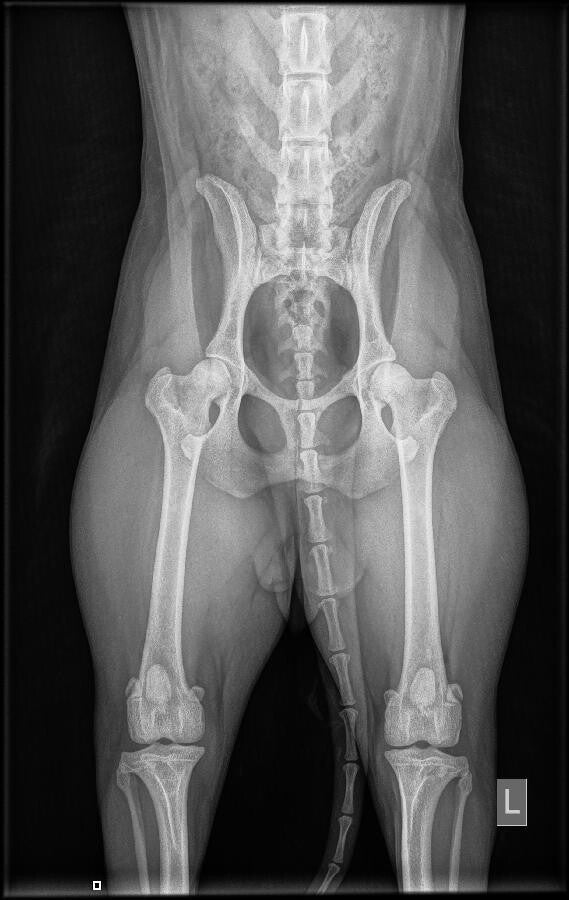

Mayla heup

Lexie 28 januari 2022 HD A

Lexie heupen 28-1-2022